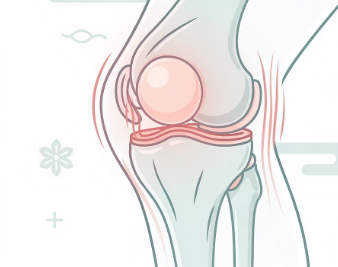

무릎에 물이 찼을 때 나타나는 증상

무릎이 눈에 띄게 붓는 느낌

무릎을 굽히거나 펼 때 불편함

압박감이나 묵직한 통증

움직일 때 뻣뻣한 느낌

열감이 동반되는 경우도 있음

증상의 정도는 원인과 염증 상태에 따라 달라집니다.